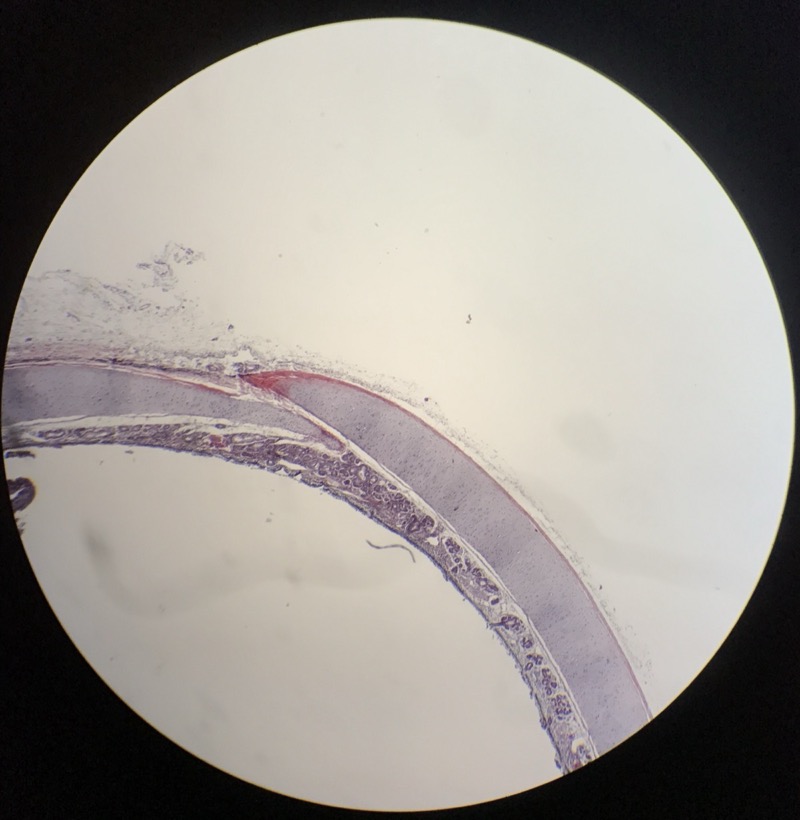

| 1:5:6 | Nagel | ![]() ![]() ![]() ![]() ![]() |